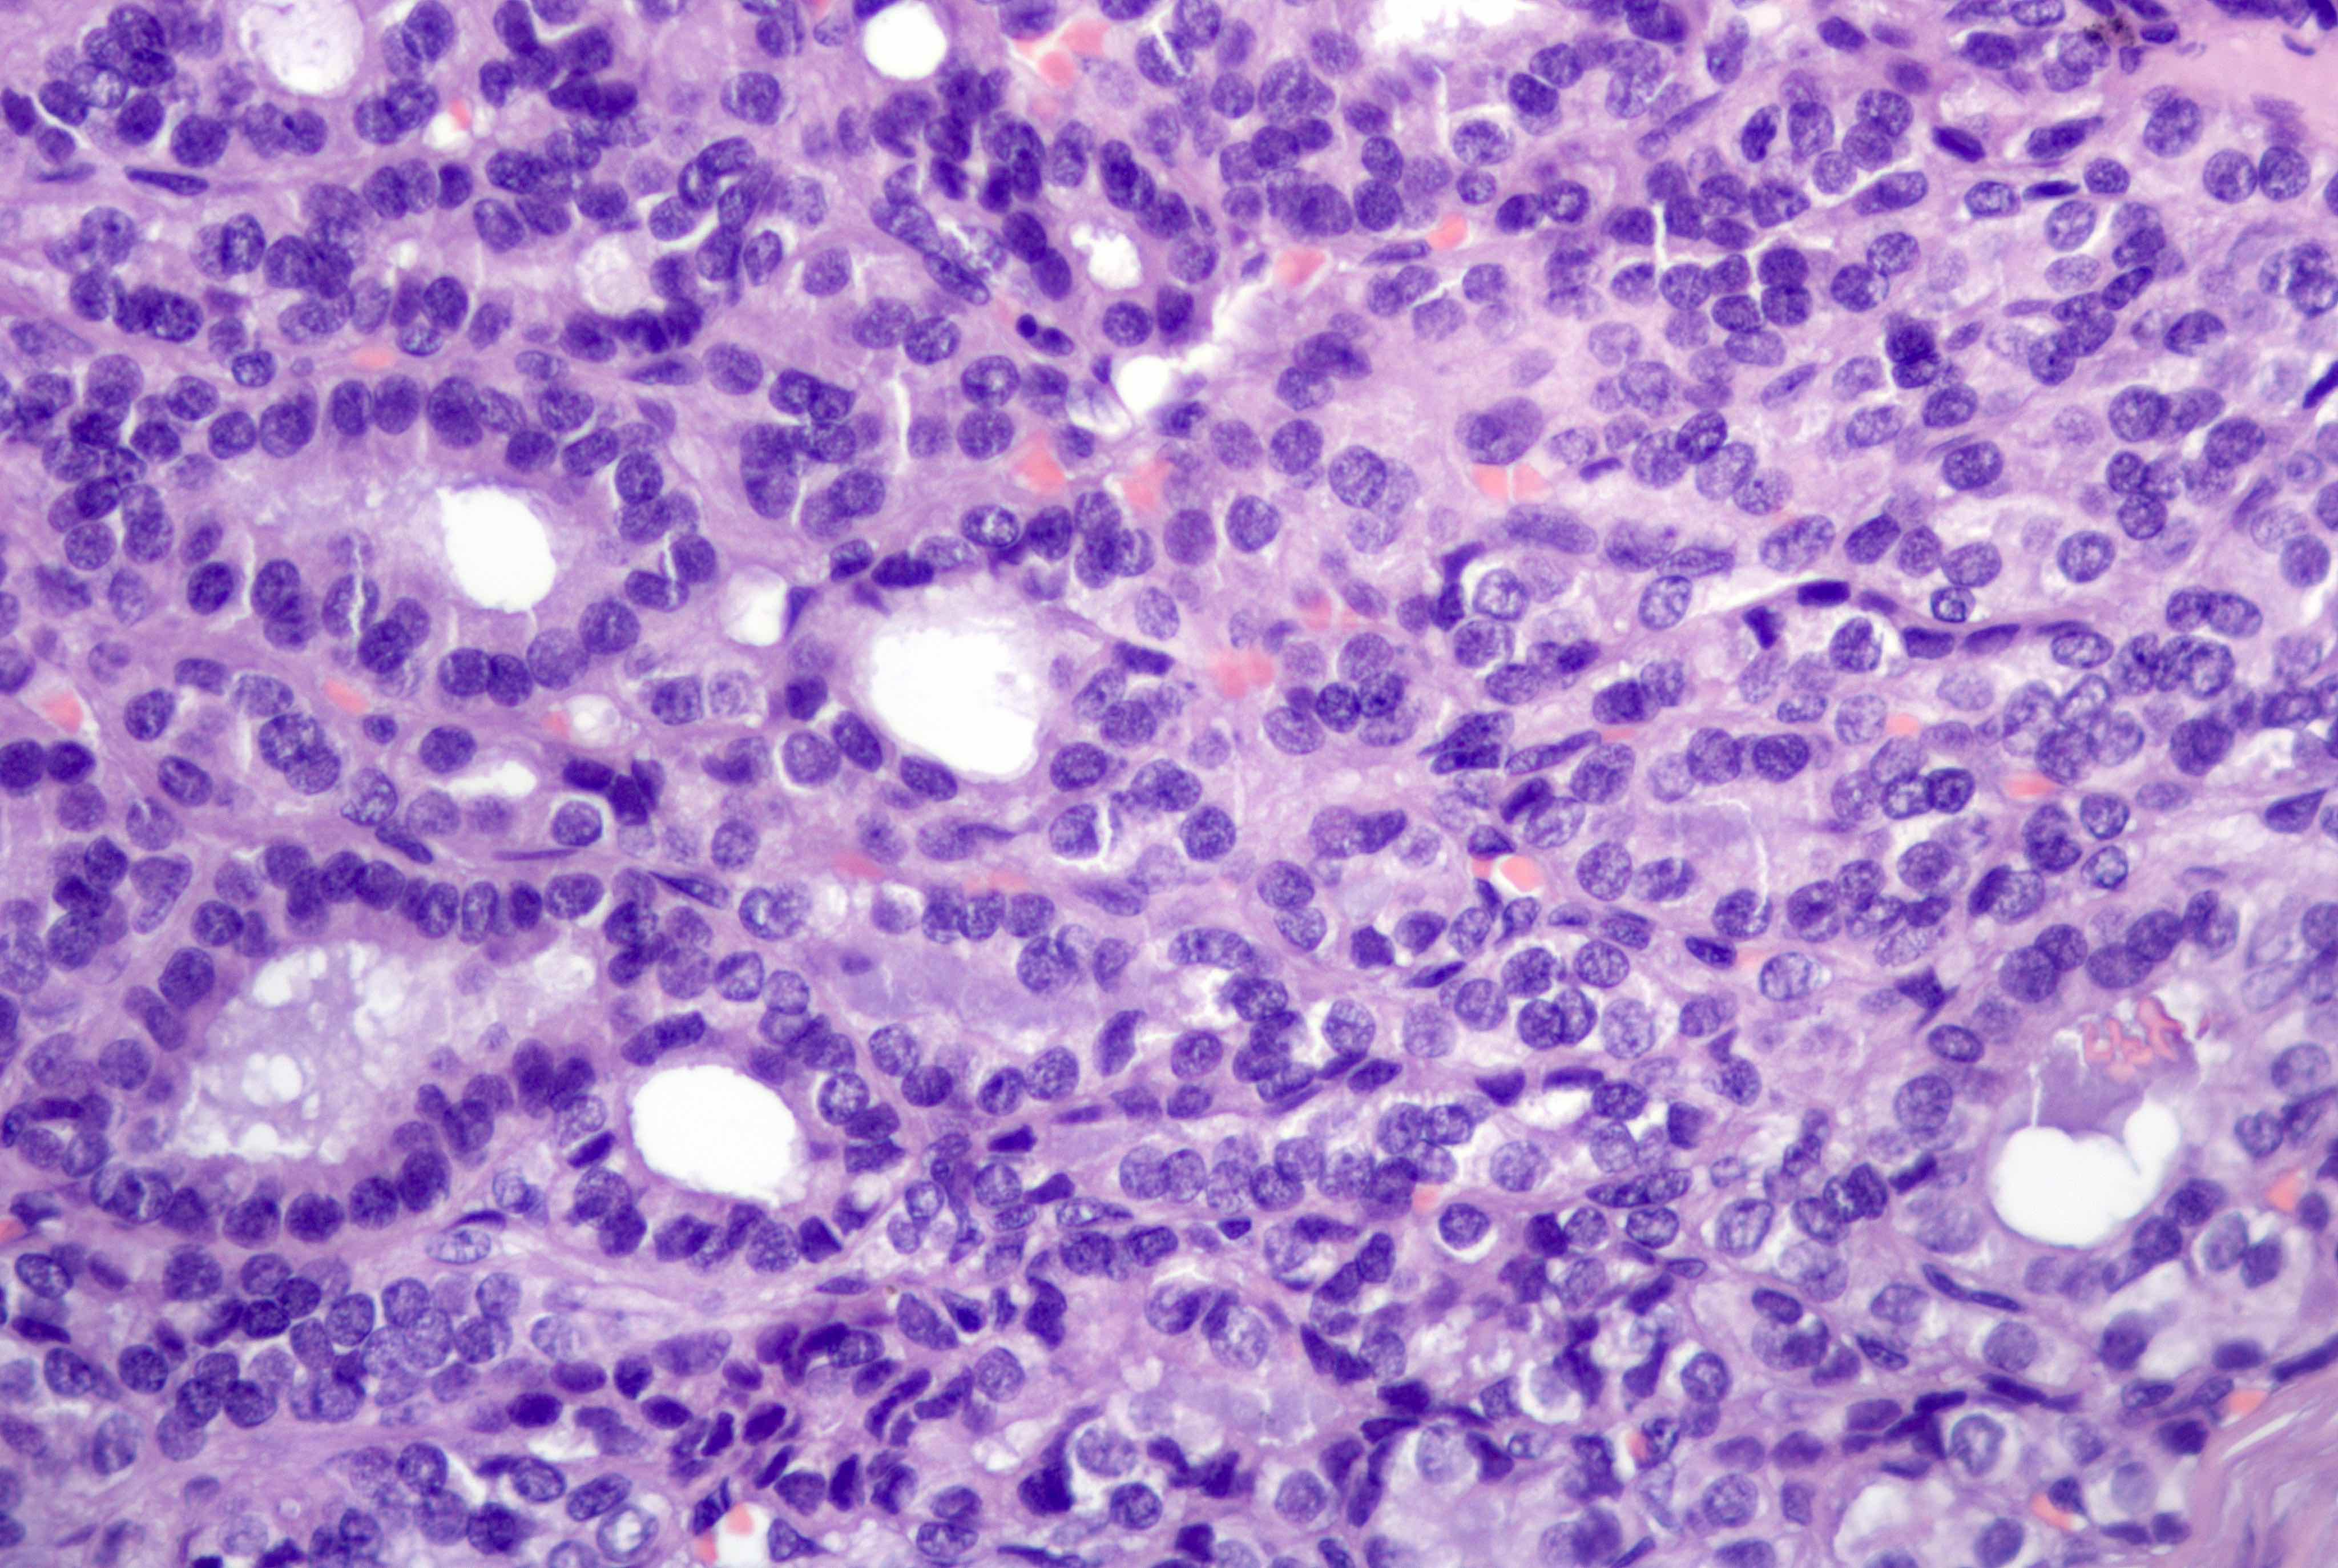

Microscopic (histologic) description

- Mixture of mature, benign tissues

- Ectodermal (most common): squamous epithelium, sebaceous glands, hair follicles, brain tissue

- Mesodermal (second most common): bone, cartilage, smooth muscle, fibroadipose tissue

- Endodermal: intestinal or respiratory epithelium, thyroid, salivary gland

- Microscopic foci of immature neuroepithelium (less than or equal to 4 foci or 21 mm2) does not warrant diagnosis of immature teratoma and will not affect prognosis (Int J Gynecol Pathol 1987;6:203)

- Fat necrosis and foreign body reaction may be seen

- Cases associated with NMDAR encephalitis usually show neuroglial tissue associated with lymphoid aggregates with germinal centers, low number of mature neurons and a hypercellular astrocyte population (Am J Surg Pathol 2019;43:949)

Microscopic (histologic) images